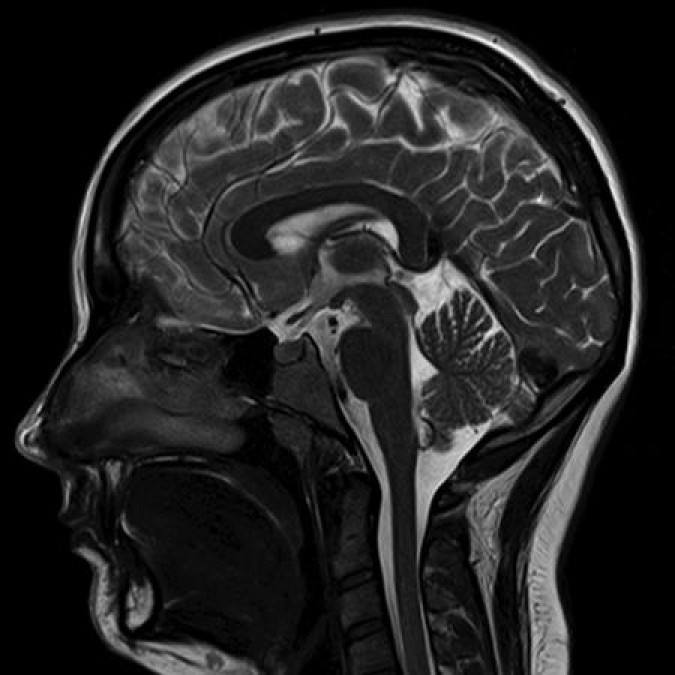

МРТ головного мозга: показания и результаты

Раздел: Визуальный дайджест